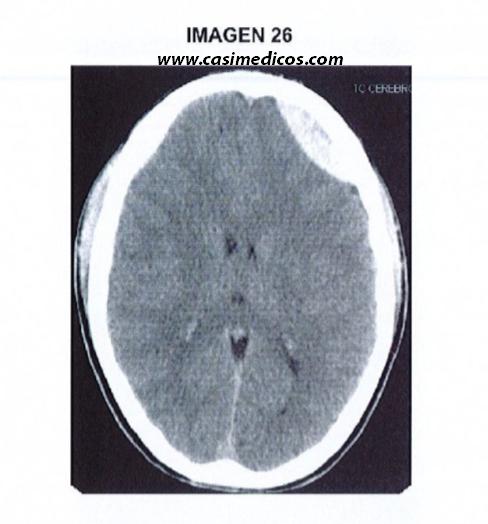

Pregunta nº 26 (vinculada a la imagen nº 26)

Joven de 17 años con traumatismo craneoencefálico secundario a choque frontal mientras jugaba al rugby sin presentar pérdida de consciencia pero sí deterioro clínico con obnubilación y amnesia. El paciente está estable tanto hemodinámica como respiratoriamente, con escala de coma de Glasgow de 15 y sin focalidad neurológica a su llegada. Se realiza TC de cráneo sin contraste intravenoso. Señale 1a respuesta FALSA:

- La lesión no es un hematoma subdural dado que aunque aparece como un coágulo hiperdenso no presenta la morfología típica ni provoca un mayor desplazamiento horizontal (efecto de masa) del que se esperaría por su tamaño.

- La lesión se corresponde con un hematoma epidural agudo en el que la duramadre, firmemente adherida, se desprende de la superficie interna del cráneo, de modo que se forma una hemorragia característica de contornos lenticulares.

- El hematoma subdural avanza por lo general con mayor rapidez y se acompaña con menos frecuencia de lesión cortical subyacente que los hematomas epidurales.

- Por lo general, los hematomas epidurales son causados por rotura de la arteria meníngea media después de una fractura del hueso temporal.

Respuesta correcta: 3.

Nos encontramos ante un hematoma epidural traumático. Vamos a analizar las opciones que se nos presentan una a una:

- Efectivamente, la lesión no es un hematoma subdural, sino un epidural. No presenta la morfología típica del subdural ni provoca mayor desplazamiento del que se esperaría por su tamaño, algo bastante característico de los subdurales (poca sangre y mucha afectación en el tejido a priori sano). Respuesta verdadera.

- En el hematoma epidural se acumula sangre por encima de la duramadre (como su propia etimología indica) al desprenderse esta de la superficie interna del cráneo. Se forma efectivamente una hemorragia de contornos lenticulares (biconvexa). Respuesta verdadera.

- El hematoma subdural avanza con MENOS rapidez que el epidural, ya que este último es consecuencia de un sangrado arterial, por tanto se expande con mayor facilidad. El hematoma subdural se acompaña de MÁS lesión cortical subyacente que el epidural; como se ha comentado antes, es característico que ante sangrados “pequeños” se produzca gran lesión del tejido cerebral subyacente. Respuesta falsa, y por tanto, la correcta.

- Efectivamente, la rotura de la arteria meníngea media por fractura del hueso temporal es el mecanismo etiológico más frecuente de los hematomas epidurales. Respuesta verdadera.